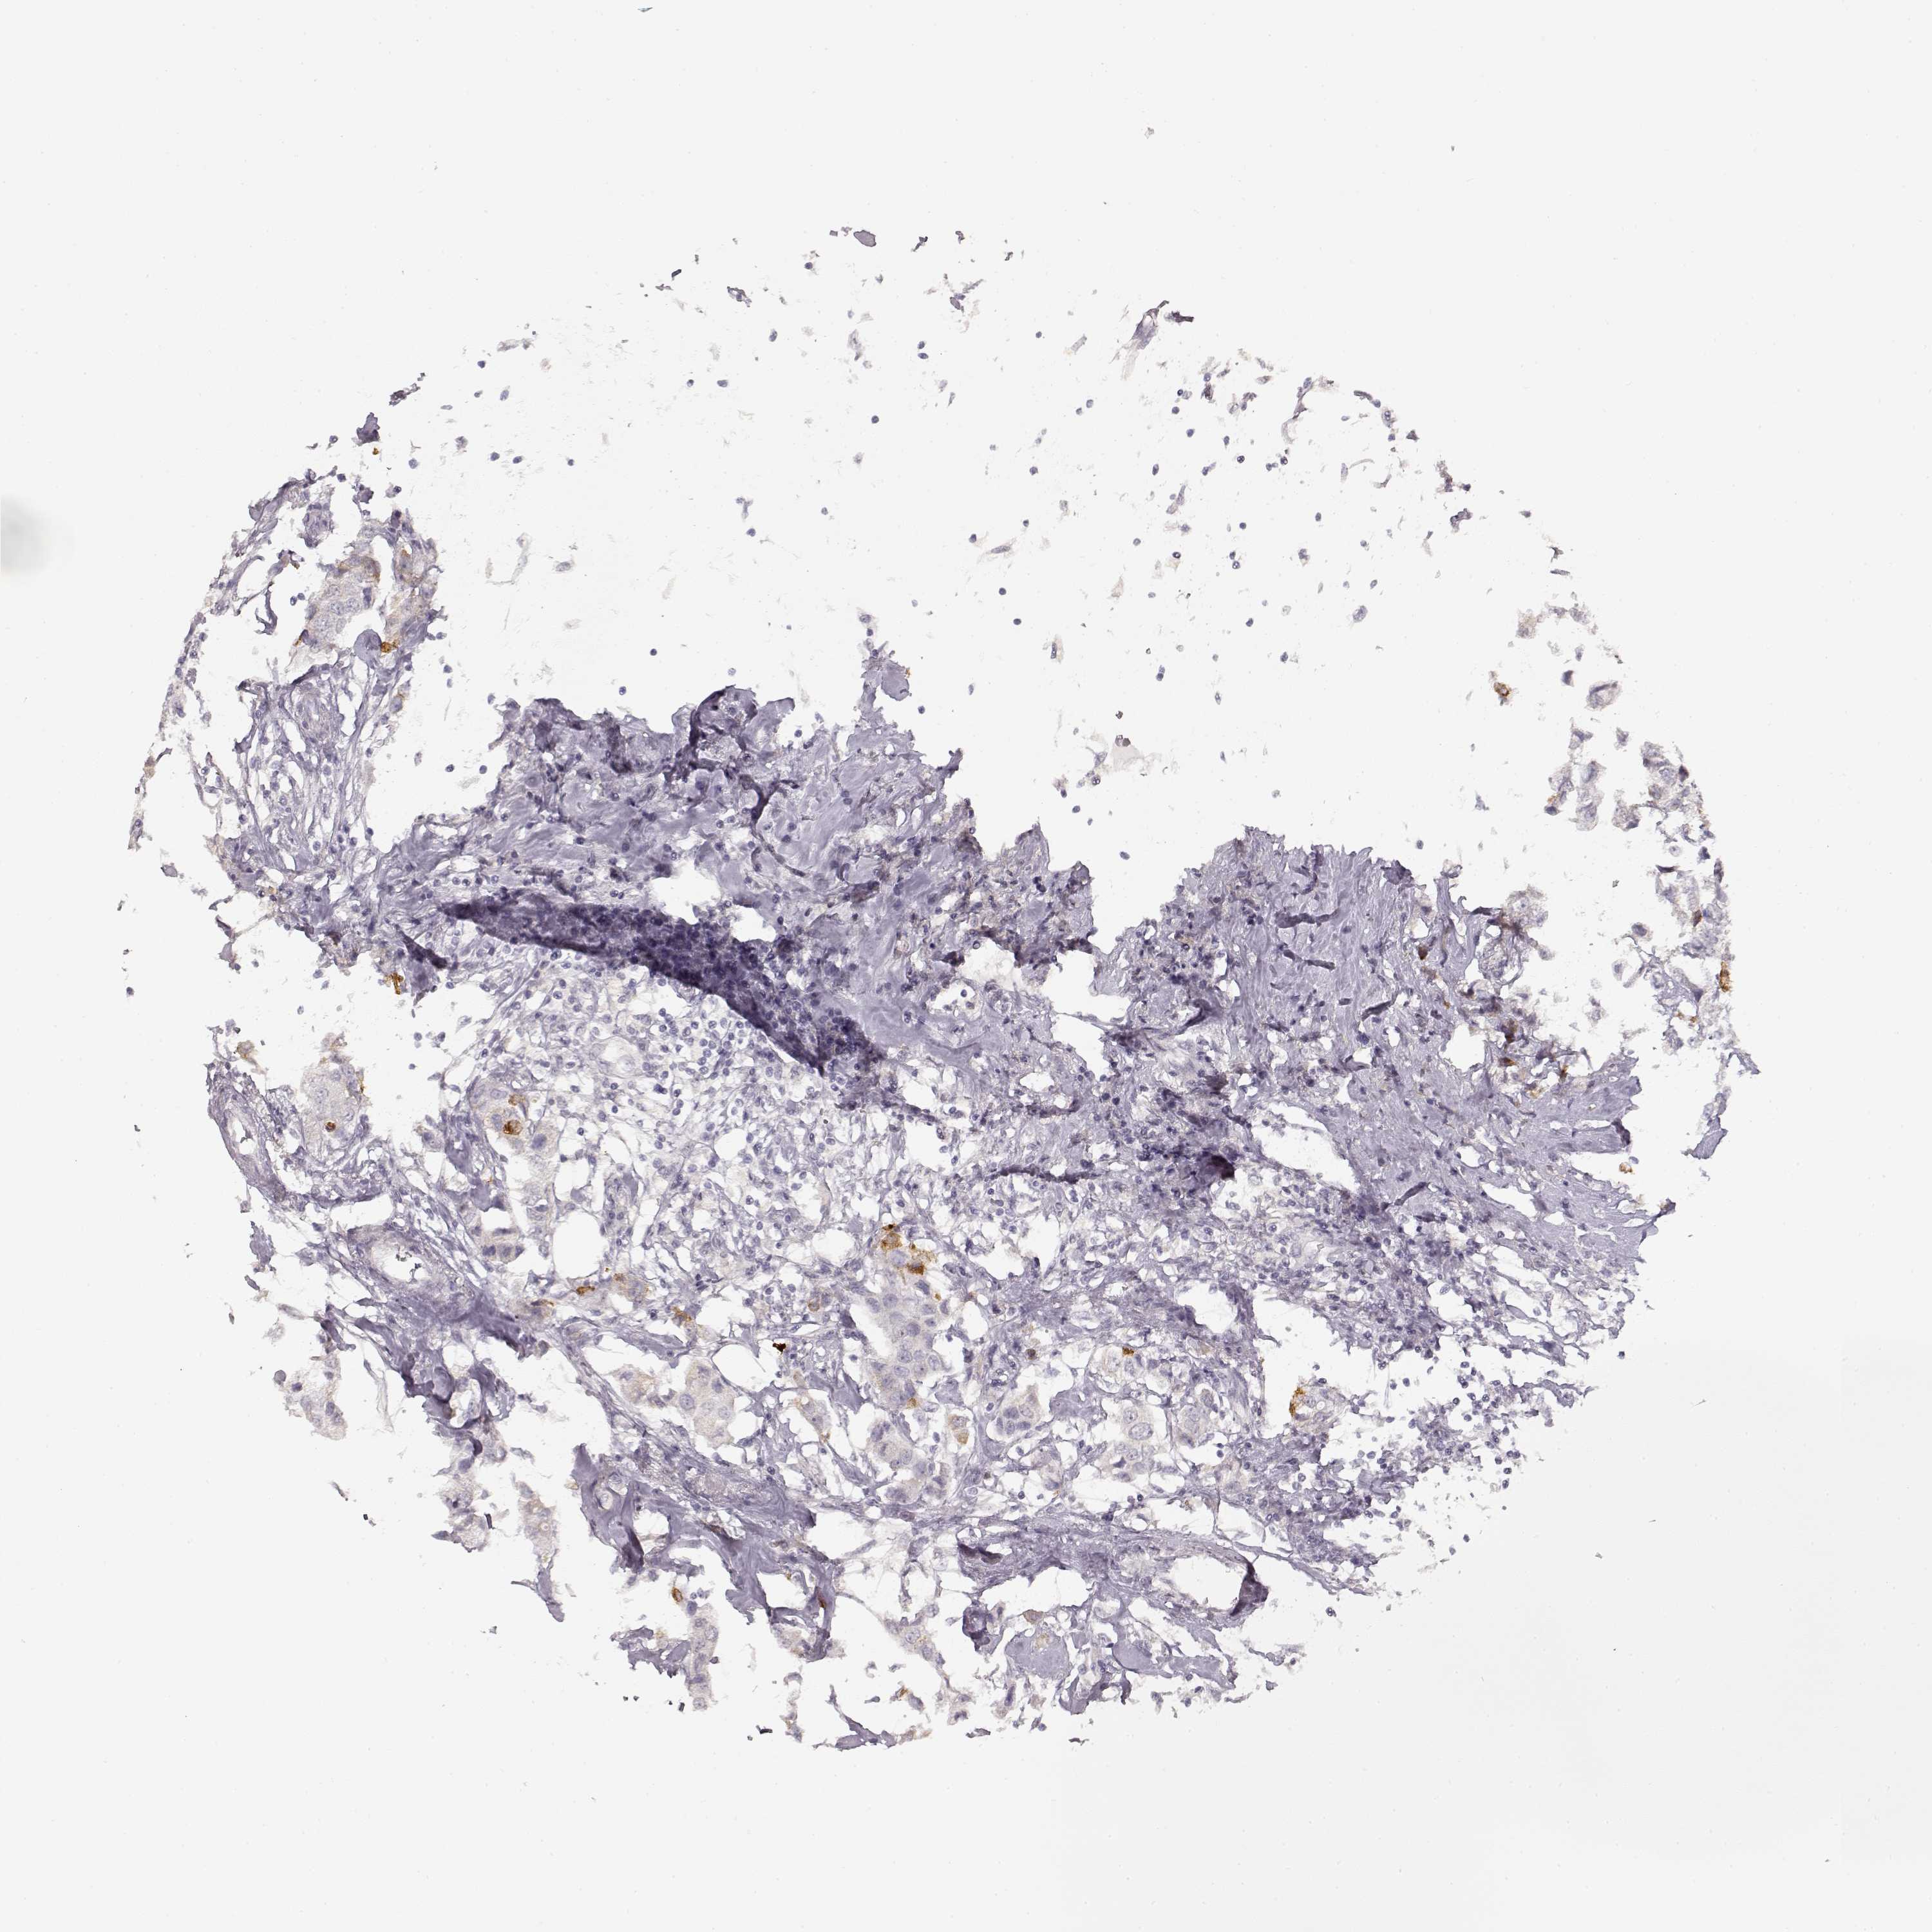

CANCER BREAST CANCER Show tissue menu

Breast cancer

Human cancer

LAMC2 is not prognostic in Breast Invasive Carcinoma (TCGA)